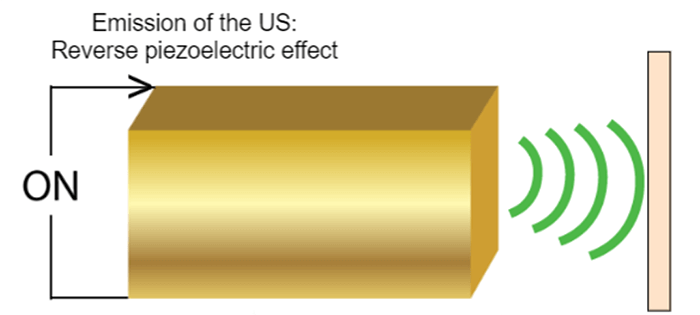

Piezoelectric materials are made of ceramic or polymer composites characterized by the reversible process, which converts the mechanical energy into electrical energy and vice versa. A transducer is composed of several or even hundreds or thousands of piezoelectric elements.

Reverse Effect

What is the difference between reverse and direct effect? And how do Piezoelectric Elements Generate Ultrasound?

The reverse effect is defined as the generation of a mechanical wave resulting from the application of an electric field. When an electric field is applied, the charge carriers are shifted in the piezoelectric materials, leading to a macroscopic change in the length of the material (inverse piezoelectric effect), thus to the emission of the ultrasound wave. The resulting sound waves propagate in the surrounding medium, where their speed varies according to the density and the elastic properties of the medium.